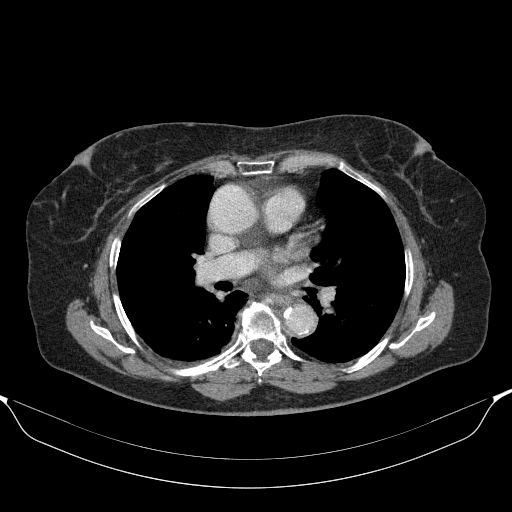

Targeted Slice 70 - Mediastinum Window Analysis (Generated vs Real Venous)

0.656

Mediastinum SSIM

49.4

Mediastinum RMSE

20.1

Mediastinum MAE

Average Mediastinum Window Metrics Across All Slices (58 slices) - Generated vs Real Venous

0.652

Mediastinum SSIM (Avg)

51.3

Mediastinum RMSE (Avg)

21.5

Mediastinum MAE (Avg)

Original VENOUS CT scan

No window - Raw intensity values

Mediastinum window (WL 40, WW 400 β†’ Low βˆ’160, High +240)